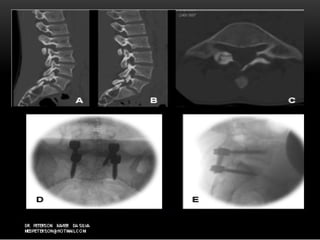

ImagensImagens

 Radiografia – AP,PERFIL,DINAMICORadiografia – AP,PERFIL,DINAMICO

 Incidência oblíqua-Incidência oblíqua- “scotty dog”“scotty dog”

 MIELOGRAFIAMIELOGRAFIA

 TCTC

 RMRM

ImagensImagens  Radiografia –AP,PERFIL,DINAMICORadiografia – AP,PERFIL,DINAMICO  Incidência oblíqua-Incidência oblíqua- “scotty dog”“scotty dog”  MIELOGRAFIAMIELOGRAFIA  TCTC  RMRM